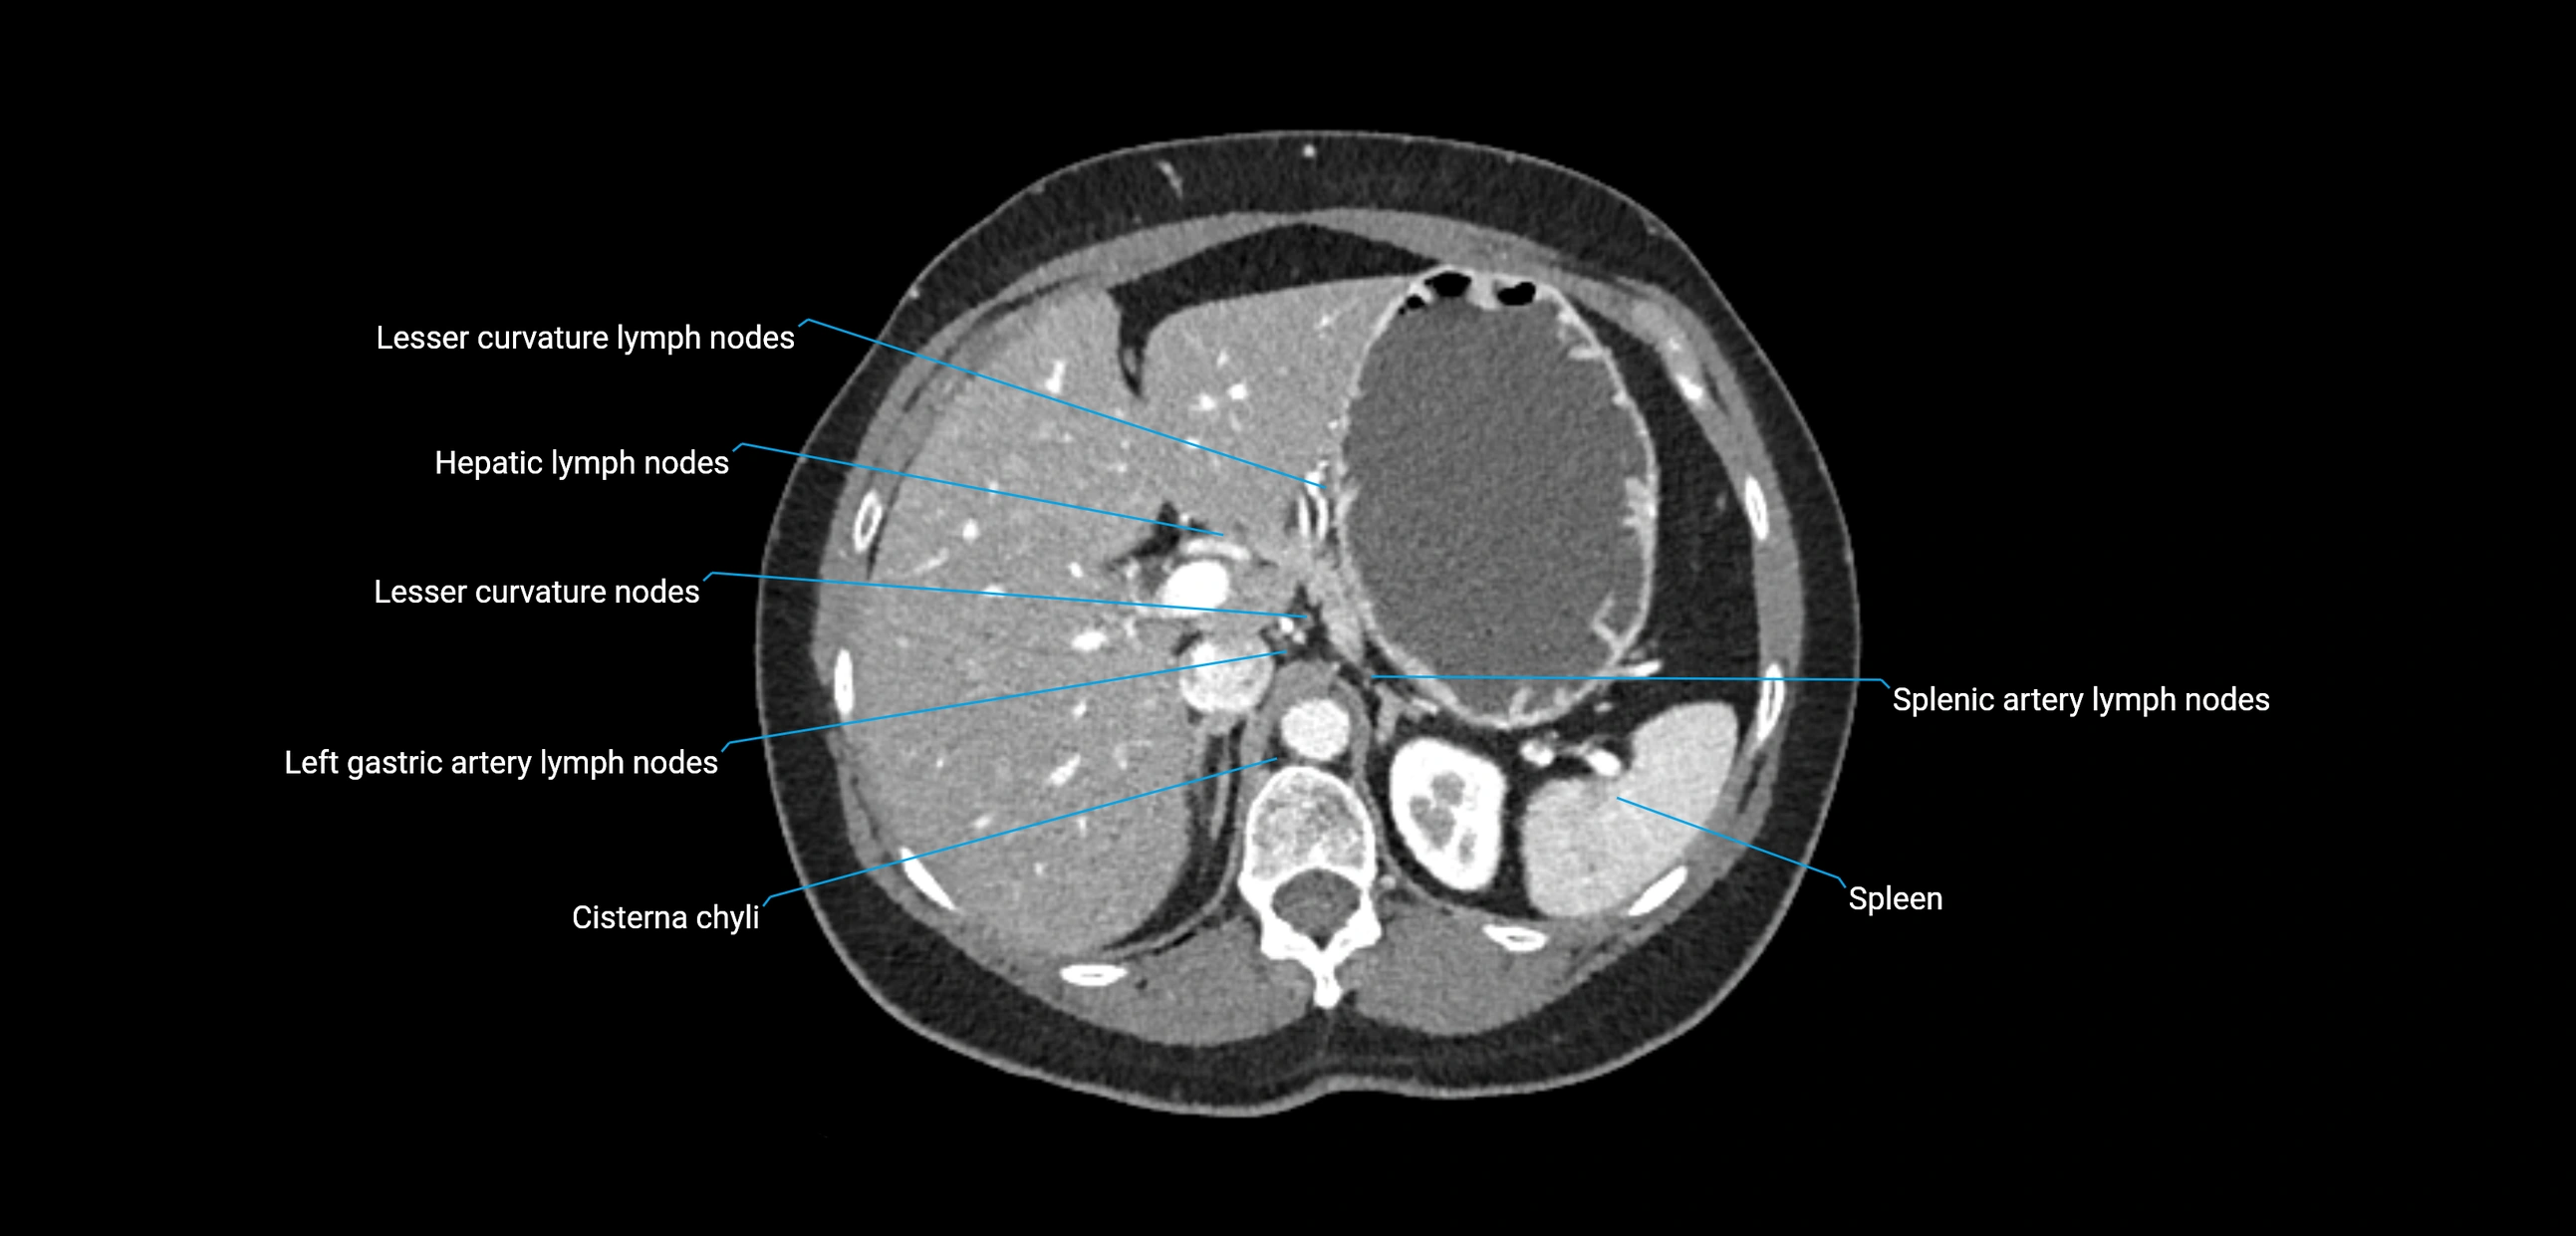

CT Appearance

CT Pre-Contrast:

• Nodes appear as soft-tissue density nodules adjacent to the aorta and IVC

CT Post-Contrast:

• Normal nodes enhance homogeneously

• Malignant nodes may show heterogeneous enhancement, central necrosis, or conglomerate formation

• Size >1 cm short axis is suspicious, though morphology and distribution are equally important